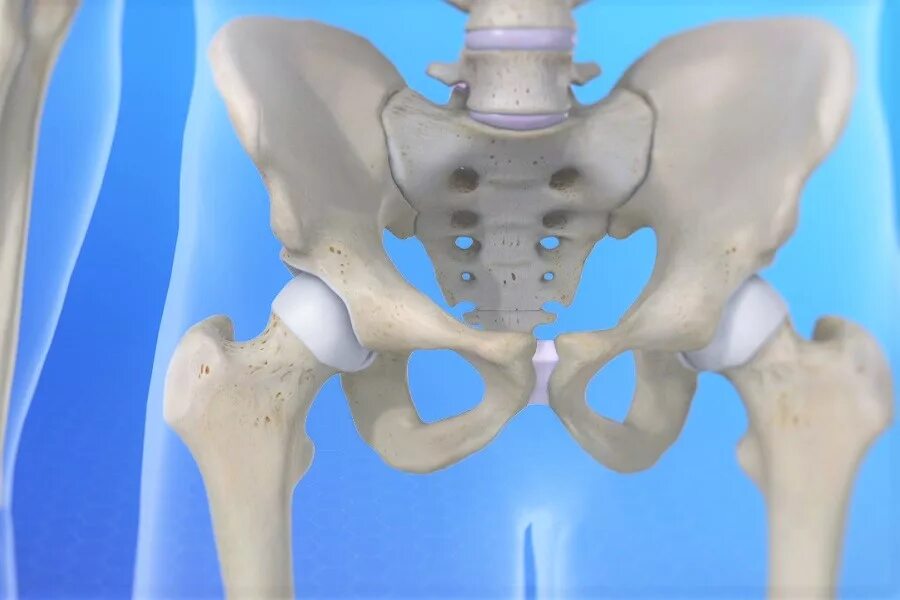

Тазобедренный сустав это